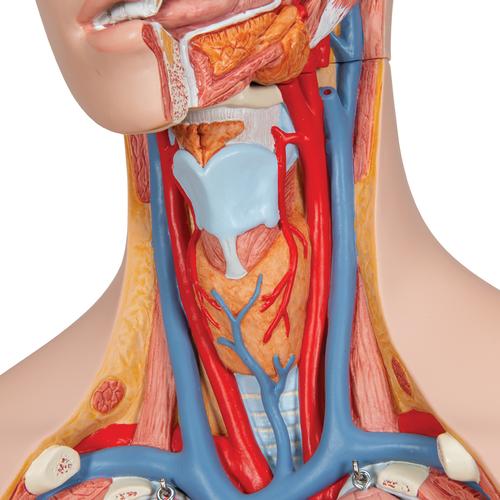

This meticulously crafted torso is expertly hand-painted with precision and made from high-quality plastic. All 3B torsos are designed and produced in Germany. This unisex human torso model features a distinctive open neck and back section extending from the cerebellum to the coccyx. It accurately depicts vertebrae, intervertebral discs, spinal cord, spinal nerves, vertebral arteries, and numerous other components in this vibrant representation of human anatomy. This human torso model includes the following detachable parts and organs: